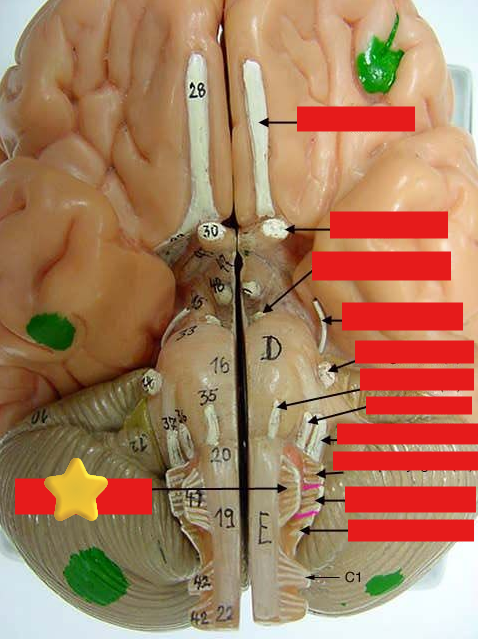

cranial nerves

12 Terms

1

olfactory

2

optic

3

oculomotor

4

trochlear

5

trigeminal

6

abucens

7

facial

8

vestibulocochlear

9

glossopharyngeal

10

vagus

11

accessory

12

hypoglossal